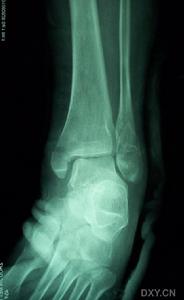

踝部骨折踝部受傷後,局部腫脹明顯,淤斑、出現內翻或外翻畸形,活動障礙,檢查可在骨折處捫局限性壓痛,踝關節正位、側位X線拍片可明確骨折的部位、類型、移位方向,對第Ⅲ型骨折,需檢查腓骨全長,若局部有壓痛。應補充照X線片,以明確高位腓骨骨折的診斷。

(1)、有明顯的外傷史。(2)上述症狀和體徵,如腫痛、畸形等。(3)X線攝片可見骨折。

踝部受傷後,局部腫脹明顯,淤斑、出現內翻或外翻畸形,活動障礙,檢查可在骨折處捫多局限性壓痛,踝關節正位、側位X線拍片可明確骨折的部位、類型、移位方向,對第Ⅲ型骨折,需檢查腓骨全長,若局部有壓痛。應補充照X線片,以明確高位腓骨骨折的診斷。